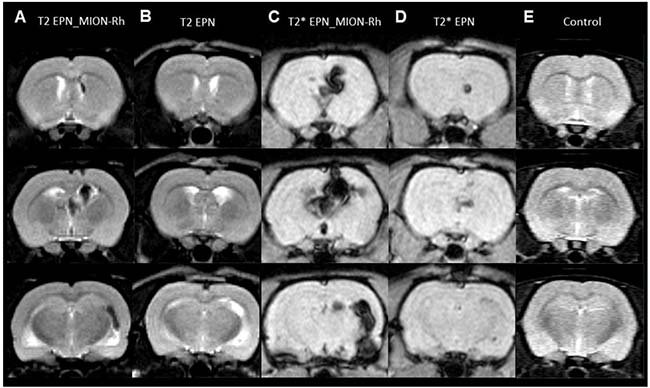

Tumor growth was monitored using MRI analysis of MION-Rh labeled EPN cells (Figures 5E, 5G, 6A, 6C); injected unlabeled EPN cells (Figure 6B, 6D); and uninjected controls (Figure 6E). In the animals that were injected with MION-Rh-labeled EPN cells, we observed ‘dark’ hypointense zones in the T2-weighted images (Figure 6A), and these zones were more evident in the T2*-weighted images (Figure 6C). In the animals injected with unlabeled EPN cells, we observed that the T2-weighted images (Figure 6B) showed hyperintense zones in the ventricles, whereas the T2*-weighted images (Figure 6D) displayed hypointense signals in the same area. The control group did not show any signal alteration during MRI (Figure 6E).

Figure 6: (A–E) MRI monitoring of in vivo EPNs. (A, B, E) T2-weighted images. (C, D) T2*-weighted images. (A, C) Detection of MION-Rh labeled EPN cells. (B, D) Detection of unlabeled EPN cells. (E) Control without any EPN cell transplantation.

MRI analysis proved to be a valuable tool when combined with effective MION-Rh labeling techniques for monitoring the migration trajectory and EPN tumor growth over defined durations. This monitoring was performed by obtaining T2- and T2*-weighted MRIs. In animals that were injected with MION-Rh labeled EPN cells, we observed the appearance of ‘dark’ hypointense zones in the T2-weighted images, which were more evident in the T2*-weighted images. The presence of MION-Rh changes the magnetic susceptibility in these regions, which accounts for these ‘dark’ zones. In animals that were injected withnon-labeled EPN cells, we observed that the T2-weighted images showed hyperintense zones in the ventricles, i.e., ventricular dilatation, whereas in T2*-weighted images, we detected hypointense signals in the same areas. Both of these signal alterations are likely due to the site of the EPN cell injection, which experienced a tissue injury followed by an edema. MRI analyses show potential for monitoring tumor growth of EPN cells efficiently labeled with MION-Rh, which functioned as an outstanding tumor contrast agent.